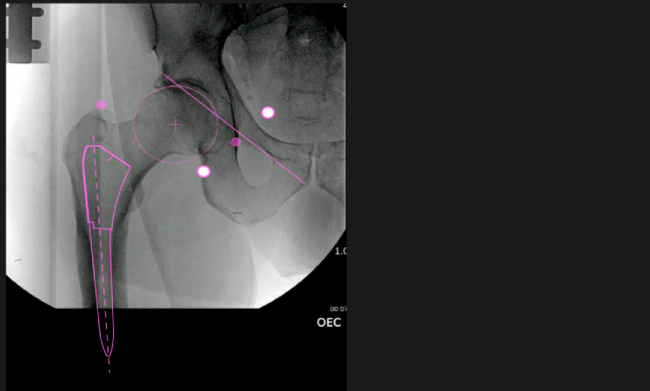

Planeación preoperatoria mediante la creación de plantillas digitales para reemplazo de cadera y análisis intraoperatorio

Mayor nivel de información intraoperatoria facilita la colocación correcta de los implantes:

Desplazamiento y offset para posicionamiento óptimo del componente (vástago) femoral.

Anotaciones digitales y herramientas de análisis de longitud de pierna.